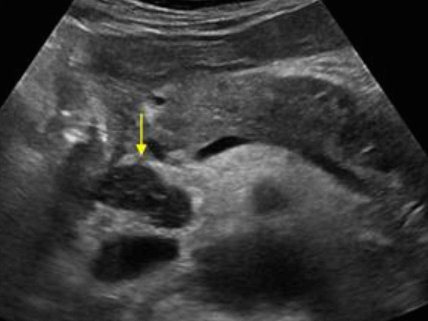

미리찌 증후군 (Mirizzi's syndrom) Mirizzi's syndrom 은 담낭경부, Hartmann's pouch 혹은 담낭관의 결석에 의해 총 간관(CHD)이 폐쇄되는 질환이다. 총 간관(CHD)이 협착되면서 상부담관은 확장되고 하부담관의 직경은 정상으로 나타난다. 증상은 폐쇄성 황달, 복부통증, 발열 등이 나타난다. 급성담낭염이 있으면서 담관폐쇄를 동반할 경우 의심해 볼 수 있다. 담낭절제술 후에 남아있는 담낭관의 결석이 총 간관(CHD)을 직접 누르거나 염증성 협착을 유발하기도 한다.

US finding

- 담낭관 또는 담낭 경부에 결석이 확인된다.

- 총간관(CHD) 또는 담낭관(cystic duct)의 확장소견이 보인다.

- 간내외 담관의 확장이 관찰된다.